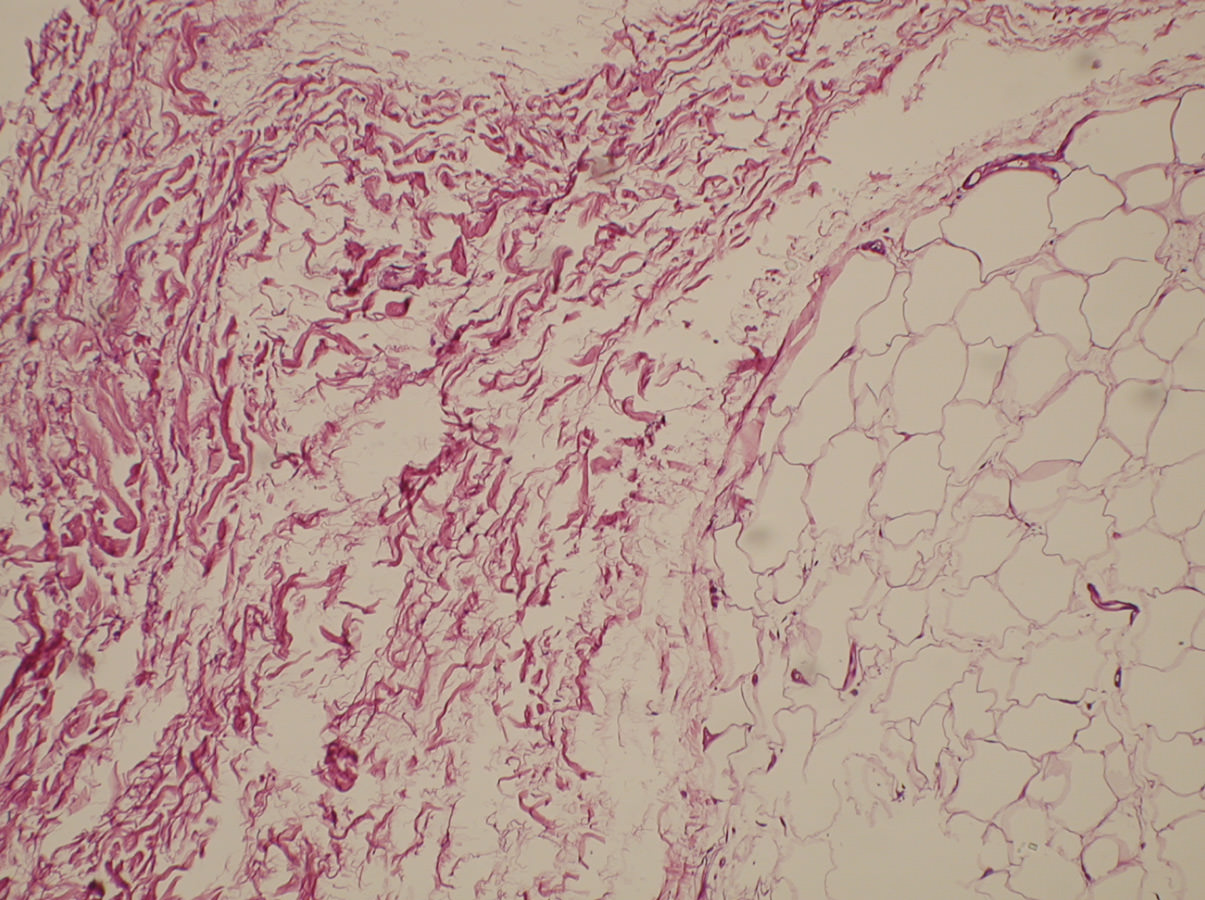

Para realizar un correcto tratamiento es necesario identificar la etiología y, solo en caso de no tener un diagnóstico de certeza, vamos a reconocer la artrofibrosis como causa de la rigidez, como un proceso de metaplasia del fibrocartílago con incremento de la fibrosis intersticial(13)(14)(Figuras 2 y 3). La historia clínica ayuda a pensar en los problemas de cicatrización, la presencia de infección superficial en el postoperatorio inmediato, los traumatismos y en la aparición de una rigidez(15)(16). Un cuadro que aparece en el postoperatorio inmediato lleva a pensar que se trata de un error quirúrgico o una rehabilitación inadecuada, mientras que en el caso de una rigidez de aparición tardía, tras un periodo de movilidad satisfactoria, nos encaminará a un proceso de infección latente o descementación.

Figura 3. Patrón de fibrosis intersticial del paquete adiposo de Hoffa en rodilla rígida.